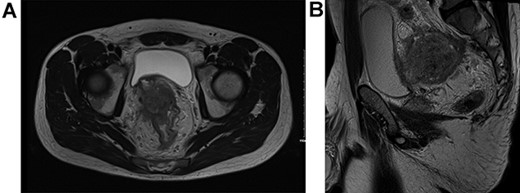

He proceeded to sigmoidoscopy, which identified a neoplasm in the upper one-third of the rectum with evidence of luminal compromise. Biopsy of this lesion at index sigmoidoscopy confirmed moderately differentiated adenocarcinoma. No synchronous tumors were identified on completion colonoscopy. Carcinoembryonic antigen (CEA) level at diagnosis was 106 ng/mL. MR staging T4BN2Mx tumor with suggestion of local bladder invasion and right pelvic side wall (Fig. 1). Computerised tomography Thorax, Abdomen and Pelvis (CTTAP) demonstrated no distant metastasis in the liver or lung but did demonstrate para-aortic lymphadenopathy. Considering the lymphadenopathy and following Multidisciplinary team (MDT) discussion, a PET CT scan was arranged, which showed these to be uninvolved but did demonstrate positive inferior mesenteric artery nodes.

T4BN2MX Upper rectal cancer (A) axial view and (B) sagittal view.